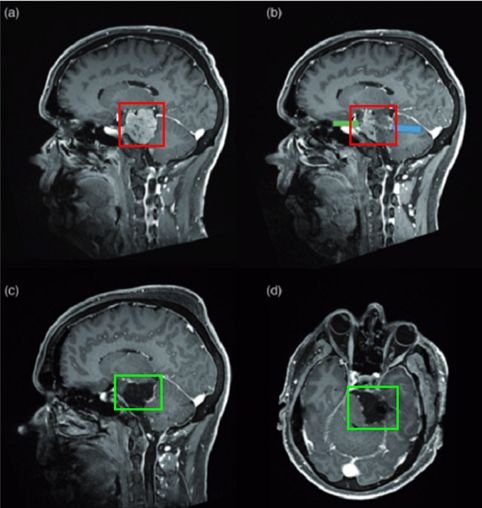

法国巴黎一位53岁男士,因三叉神经痛合并三叉神经感觉减退,在当地神经外科医院Lariboisiere医院,查出左侧较大岩斜脑膜瘤(27立方厘米)。脑磁共振(mri)显示可见明显的轴外肿瘤,岩斜向外扩张,对脑干有明显的挤压效应。

1、术前栓塞:用1毫升氰基丙烯酸酯胶(Glubran,Glubran-2,GEM,Viareggio,Italy)碘油(4ml of lipiodol)堵塞供血动脉,造影结果良好,无并发症。术后脑MR显示脑膜瘤部分断流,无脑水肿。

(患者脑血管造影图)

2、二天手术切除:颞部开颅术和前岩部切除术。脑膜瘤在肿瘤切除的不同阶段交替进行超声抽吸和周围结构的仔细解剖,从血管的角度观察,硬脑膜边缘被切断以完成肿瘤的断流。手术切除是完全的(辛普森I级切除),全部周围的颅神经IV、V、VII、VIII等均保存完好,患者术后神经功能完好。

1、术后神经影像学检查

术后CT扫描未显示任何术后并发症。术后MRI显示脑膜瘤几乎完全切除,海绵窦后部有少量残留。